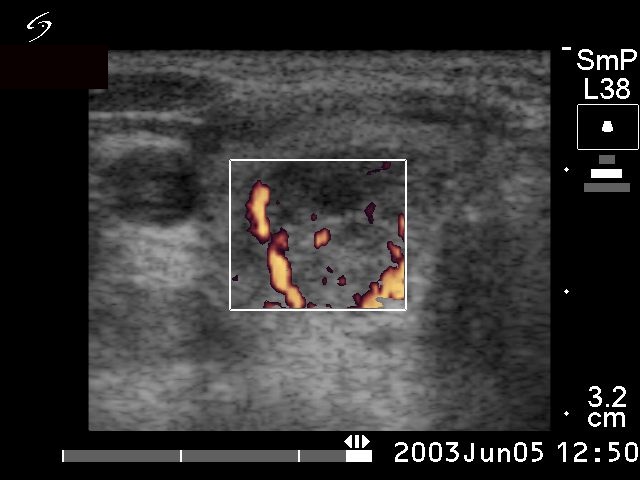

The ultrasound presentation of the left case is equivocal. A solitary, not regularly geometrical nodule is presented which did not display halo sign. Although there were signs of a perinodular blood flow, most vessels demonstrated in the image run not within the rim of the lesion but run from the border into the lesion.

The ultrasound appearance of the follicular tumor is almost pathognomic: a large, solitary nodule presents halo sign and perinodular blood flow.